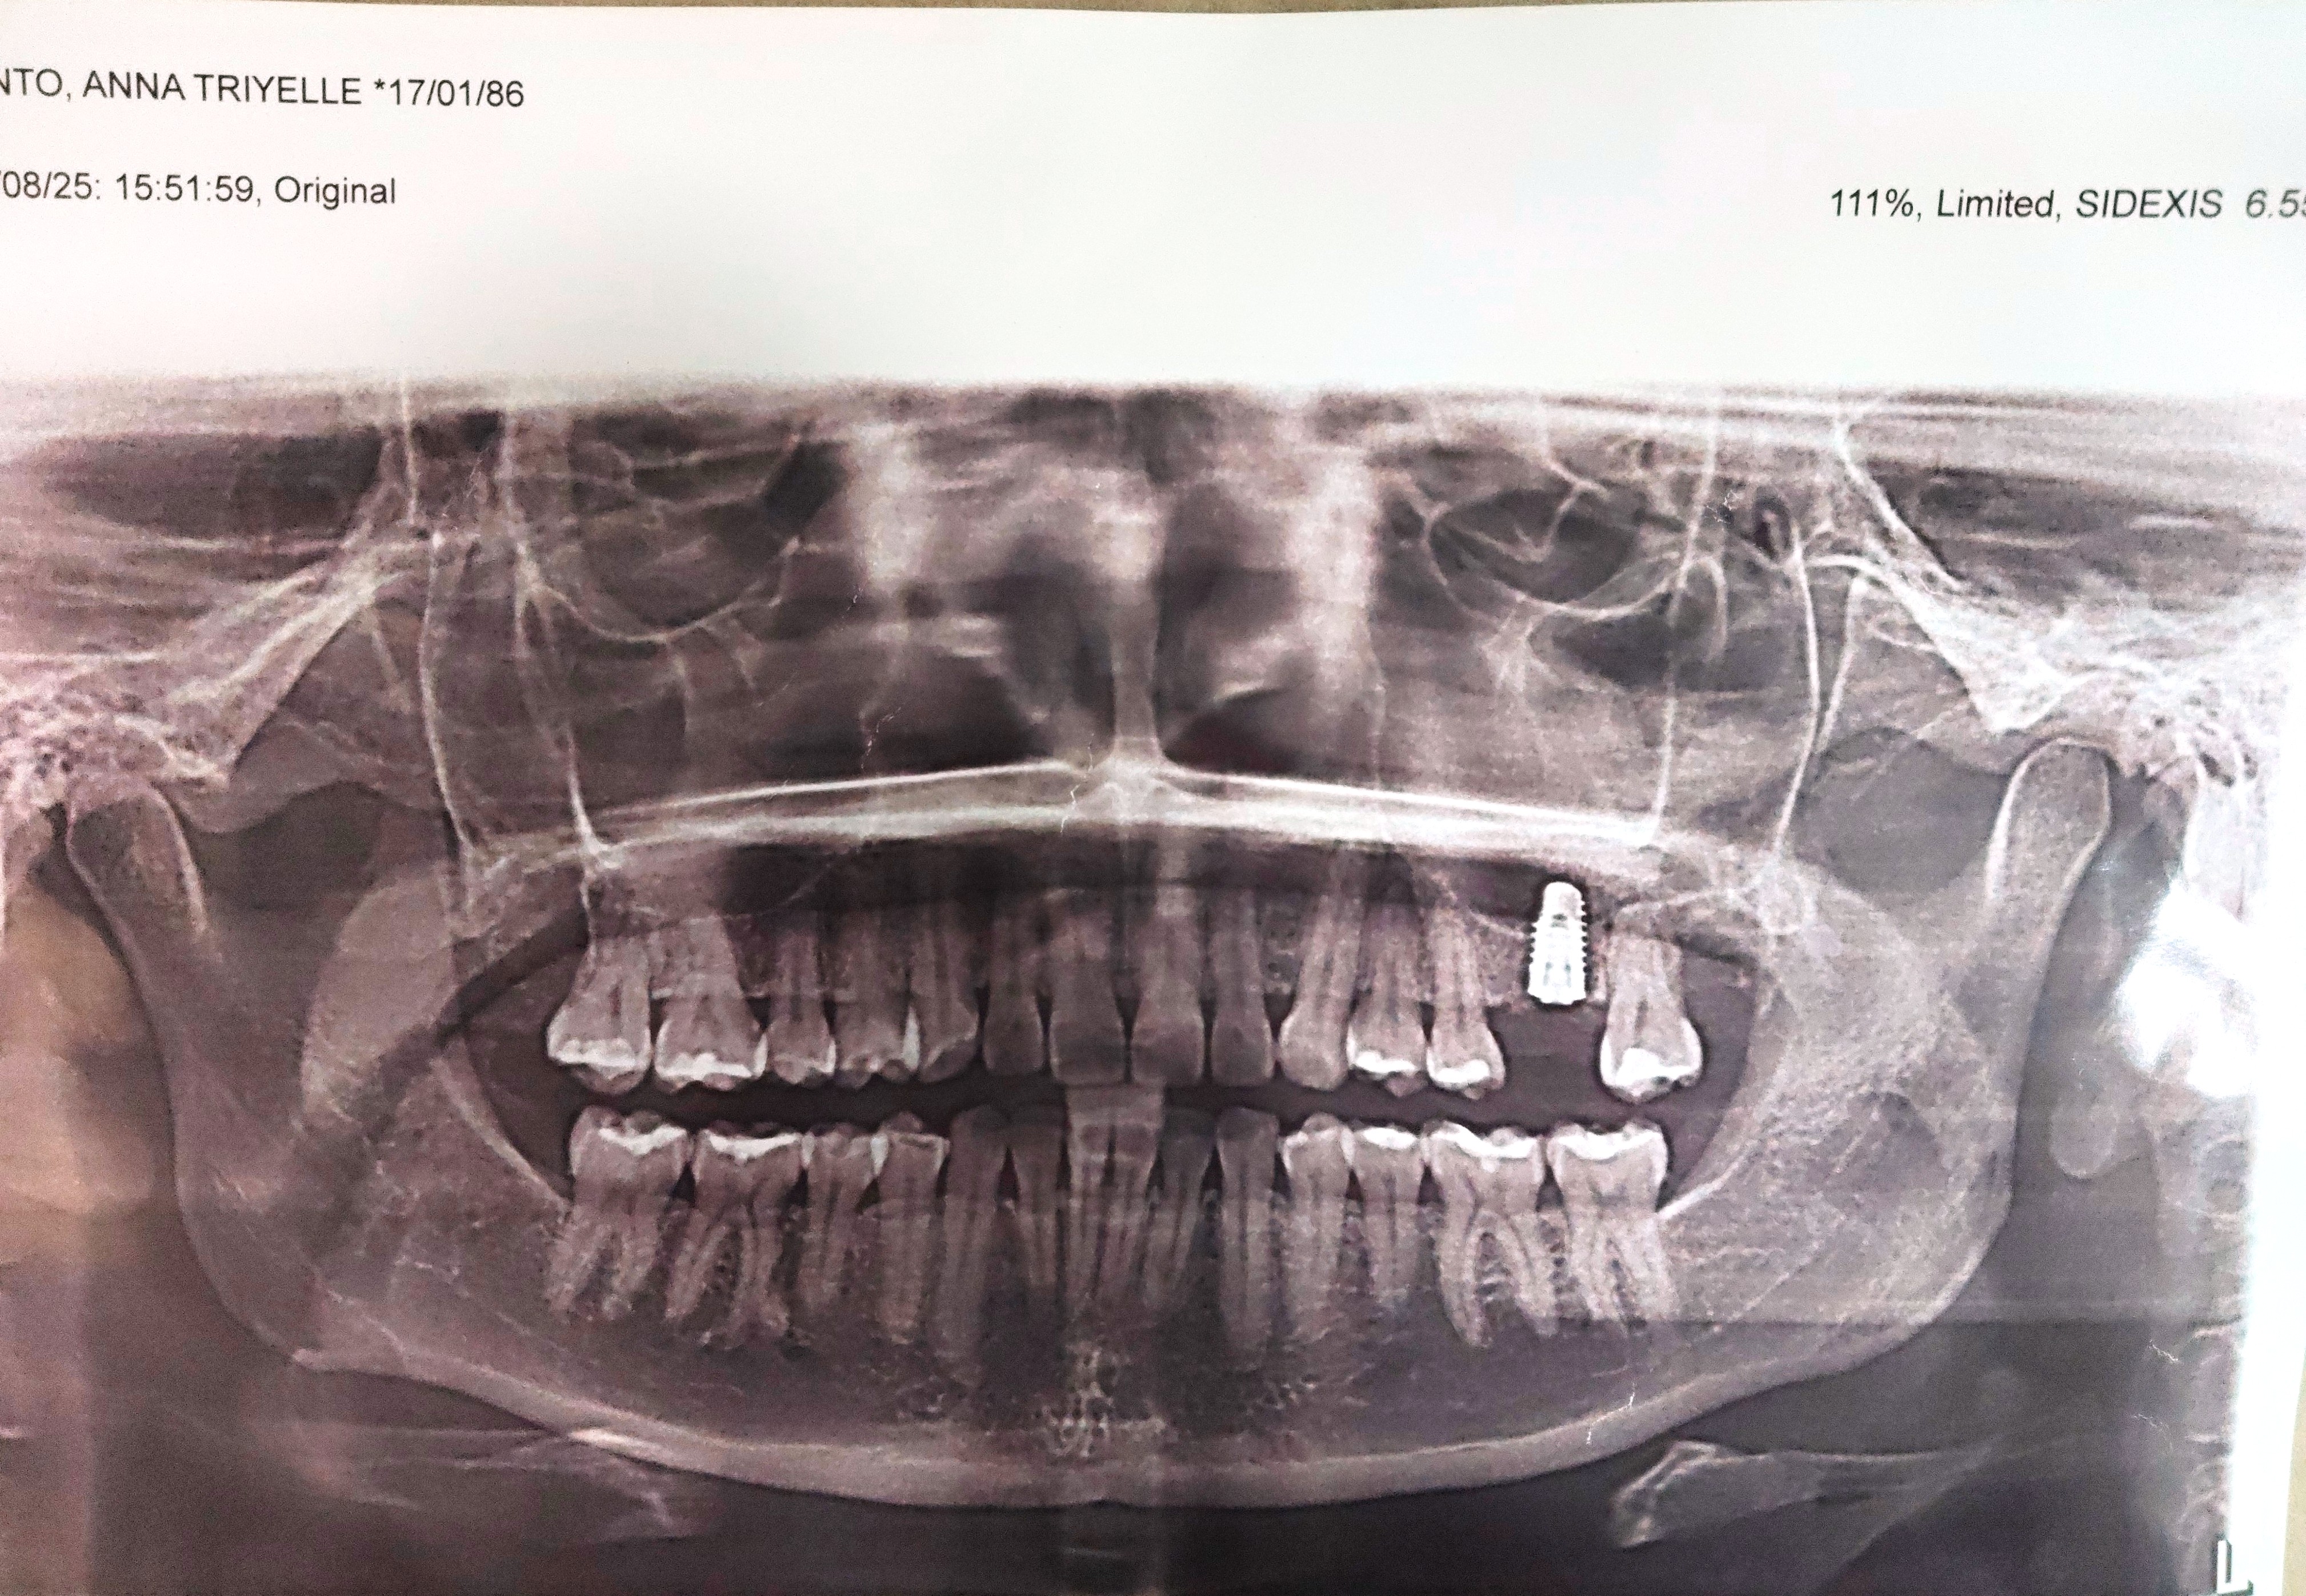

- Anna Triyelle

- January 17, 1986

- 06/21/25 OP mild 08/07/25 Implant #26 size 5.3x 10mm IT with screw cover DO bone- cortical and cancellous bone 1cc membrane Titan guide 15x20mm *sinus perforation 2 tubes cgf 10 tubes PRF lidocaine x5 carps RX: celecoxib 400 mg. prednisone 10mg, tranexamic 500mg co-amoxiclav 625mg 10caps, saline spray Odontectomy #18/ 28 08/19/25 RECALL 11/12/25 RECALL 11/18/25 HA installed 5.3mmx2mm after 3 weeks. laser implant location 01/10/26 scanning for implant crown 01/20/2026 Installed crown Implant + zircomia cement: rely -x 04/29/2026 OP w/airpolish xray